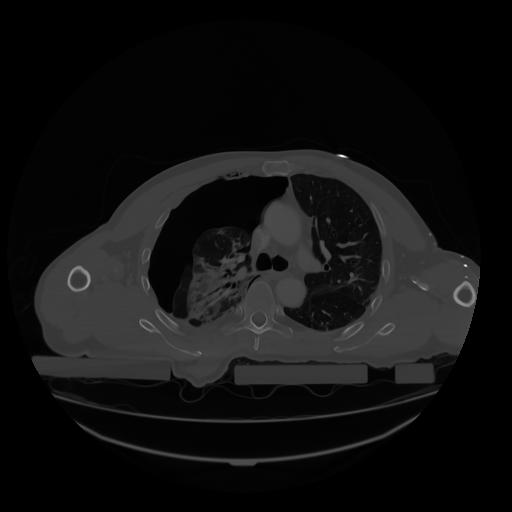

28 CUERPO,CE,Vol,2.0,CUERPO,,